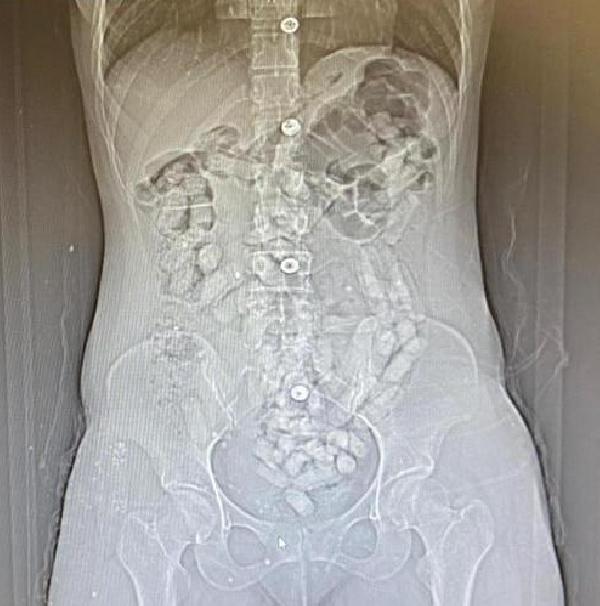

Savcılıktan alınan kararla götürüldükleri hastanede yapılan tomografi çekiminde, Khadıjeh S.'nin mide ve bağırsak bölümünde 31 parça halinde yaklaşık ağırlığı 252,52 gram ile Samıra T.'nin de 64 parça halinde 440,78 gram olmak üzere toplam 95 parça halinde 693,3 gram Afyon sakızı ele geçirildi. Gözaltına alınan şüpheliler, emniyetteki sorgularının ardından 'Uyuşturucu madde ticareti yapmak' suçundan adliyeye sevk edildi. Allahnıaz S. adli kontrol şartıyla serbest kalırken; Khadıjeh S., Samıra T. ve Raheleh Y. tutuklandı. (DHA)